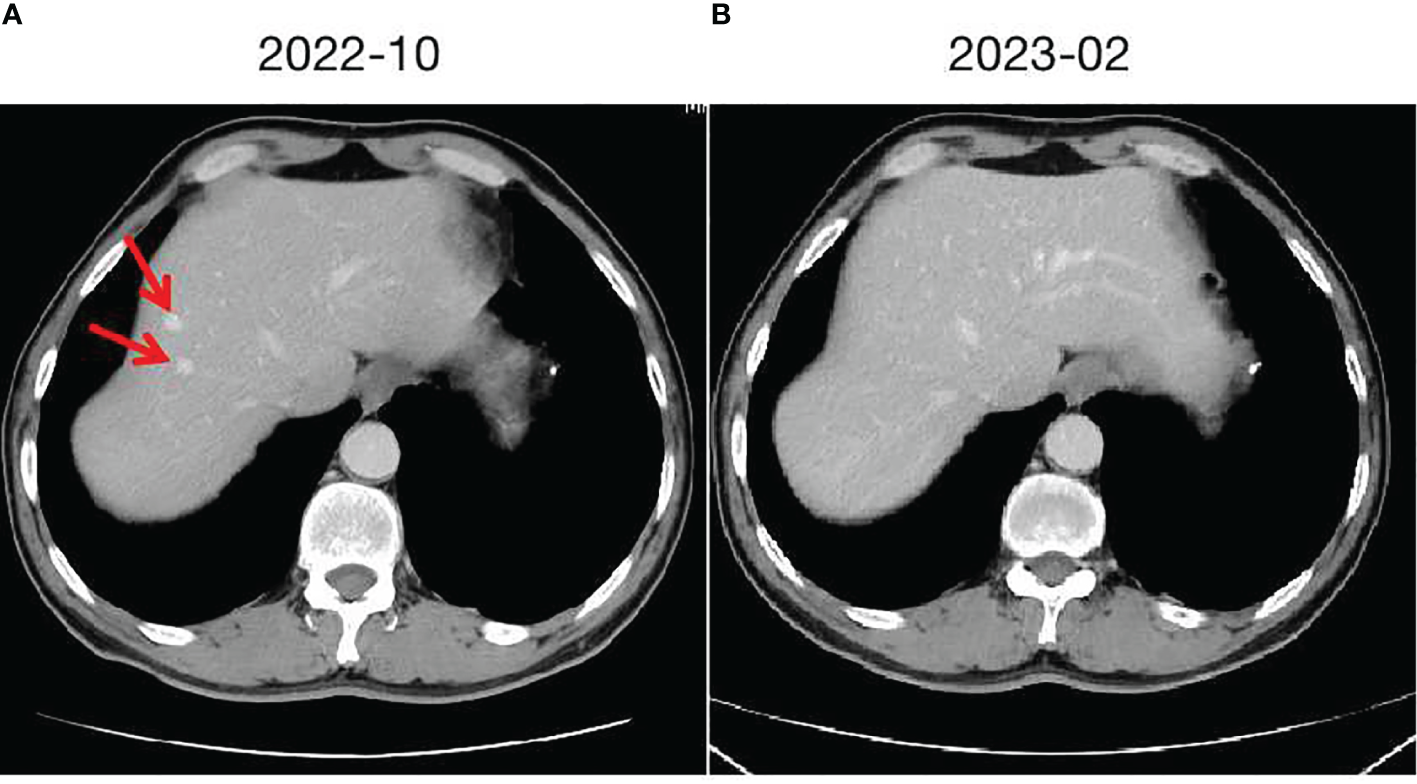

Figure 2

Hepatic cavernous hemangioma and changes. (A) taken in October 2022, shows the initial imaging findings of two hepatic cavernous hemangiomas in the left liver. (B) taken in February 2023, demonstrates the changes following discontinuation of Camrelizumab, with the hepatic cavernous hemangioma almost disappearing.

In September 2020, a middle-aged male presented to the hospital with dizziness and headaches. Brain MRI revealed an abnormal mass in the brain, suggestive of a metastatic tumor. Apart from neurological symptoms, there is mild cough without sputum, no chest tightness or chest pain, no fever or sweating, no diarrhea or constipation. The patient has a history of hypertension for 10 years. The highest recorded blood pressure was 175/105mmHg. Currently, the patient is taking oral antihypertensive medication (Valsartan capsules, 80mg/d), and the blood pressure is controlled within the range of 130-140/90-100mmHg. No cerebrovascular diseases or coronary artery disease. The patient denies any infectious diseases such as hepatitis or enteritis. There is no history of trauma, surgery, or blood transfusion. No known food or drug allergies. The patient has a smoking history of 35 years, consuming 10 cigarettes per day. Occasional alcohol consumption.Vital signs are stable. Specifically:H 177cm, W 60kg, HR 91/min, BP 137/95mmHg.Laboratory tests: WBC 7.64×109/L (4-10×109/L), RBC 5.17×1012/L (4-5.5×1012/L), Hb 128g/L (120-160g/L), PLT 232×109/L (100-300×109/L), CEA 103.6ng/ml↑ (<3.4ng/ml), CA24-2 63U/ml↑ (<15U/ml), other tumor markers are within normal range. Further evaluation with whole-body PET/CT indicated a lesion in the left lung measuring 40×35mm, accompanied by lymph node and mediastinal metastasis, as well as multiple brain metastases. A CT-guided biopsy was performed on the lesion in the left lung, and the pathological analysis indicated poorly differentiated adenocarcinoma. A 10-gene test for lung cancer revealed a KRAS missense mutation (G13D, 13.91%), while no mutations were found in the remaining genes (EGFR, ALK, ROS1, BRAF, NRAS, HER2, PIK3CA, RET, MET). The PD-L1 positivity rate was 10%.The clinical stage is cT2N2M1, stage IV. A multidisciplinary consultation within the hospital was conducted, considering the patient’s current multiple brain metastases and significant symptoms. It was recommended to prioritize whole-brain radiation therapy (WBRT) and symptomatic treatments such as intracranial pressure reduction and nutritional support. After symptom control, systemic treatment and radiation therapy for the primary lesion were suggested. Consequently, from October 2020 to November 2020, the patient received WBRT using 6MV X-rays, delivering a dose of 30Gy/10f/2w to 95% of the planning target volume (PTV). During this period, treatment for dehydration and intracranial pressure reduction was administered. Following the completion of radiation therapy, the patient experienced a significant improvement in symptoms, including reduced dizziness and headaches. The ECOG PS improved from a score of 3 to 1.Although the patient was initially diagnosed with stage IV disease, distant metastases were limited to the intracranial region. After receiving cranial radiation therapy and supportive care, the intracranial lesions were well controlled, and the patient’s general condition remained good. The patient expressed a strong willingness for treatment. Taking reference from the KEYNOTE189 and CAMEL studies, after discussing with the patient, a systemic treatment regimen comprising platinum-based doublet chemotherapy in combination with PD-1 inhibitor was administered. From December 2020 to June 2021, the patient received 8 cycles of the PP regimen chemotherapy (Pemetrexed 500mg/m² iv day 1, Carboplatin AUC5 iv day 1, every 3 weeks) combined with PD-1 inhibitor therapy (Camrelizumab 200mg, every 3 weeks). During the second to fourth cycles of treatment, concurrent radiotherapy was administered. The specific radiotherapy plan consisted of 6MV X-rays, delivering a dose of 60Gy/30f/6w to 95% of the planning target volume (PTV), and the treatment toxicity was tolerable. Following the completion of concurrent chemoradiotherapy, the therapeutic evaluation of the primary lesion in the chest and intracranial lesions, according to RECIST v1.1 criteria, showed a partial response (PR). Maintenance treatment was initiated in July 2021, with the following regimen: Pemetrexed 500mg/m² iv day 1, Bevacizumab 500mg iv day 1, and Camrelizumab 200mg every 3 weeks. Regular follow-up examinations were conducted every 2 months, and the therapeutic evaluation remained stable disease (SD). In October 2022, a liver nodule was discovered in the left liver lobe on abdominal CT (Figure 2A). A further ultrasound-guided biopsy was performed, and the pathological results confirmed hepatic cavernous hemangioma. Similar to the previous patient, a multidisciplinary consultation was conducted, and it was determined that the liver nodule was likely a drug reaction to Camrelizumab. Therefore, Camrelizumab was discontinued starting from November 2022, and maintenance treatment with Pemetrexed and Bevacizumab was initiated using the same dosage and cycle as before. Subsequently, the hepatic cavernous hemangioma disappeared (Figure 2B), and no further drug-related adverse reactions occurred. The clinical response continued to be evaluated as stable disease (SD).